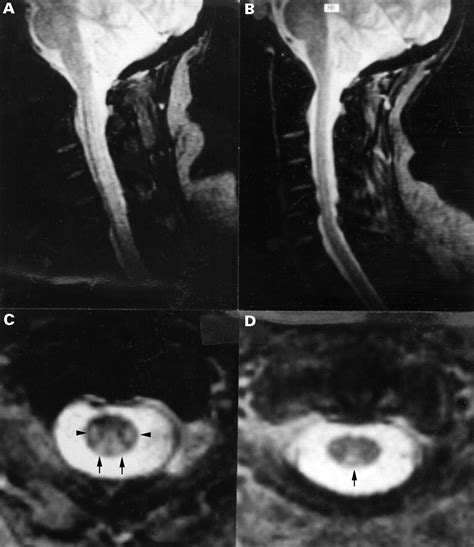

• MRI of the Spine: An MRI can reveal the classic "inverted V" sign in the posterior columns of the cervical spinal cord, which is highly indicative of SCD.